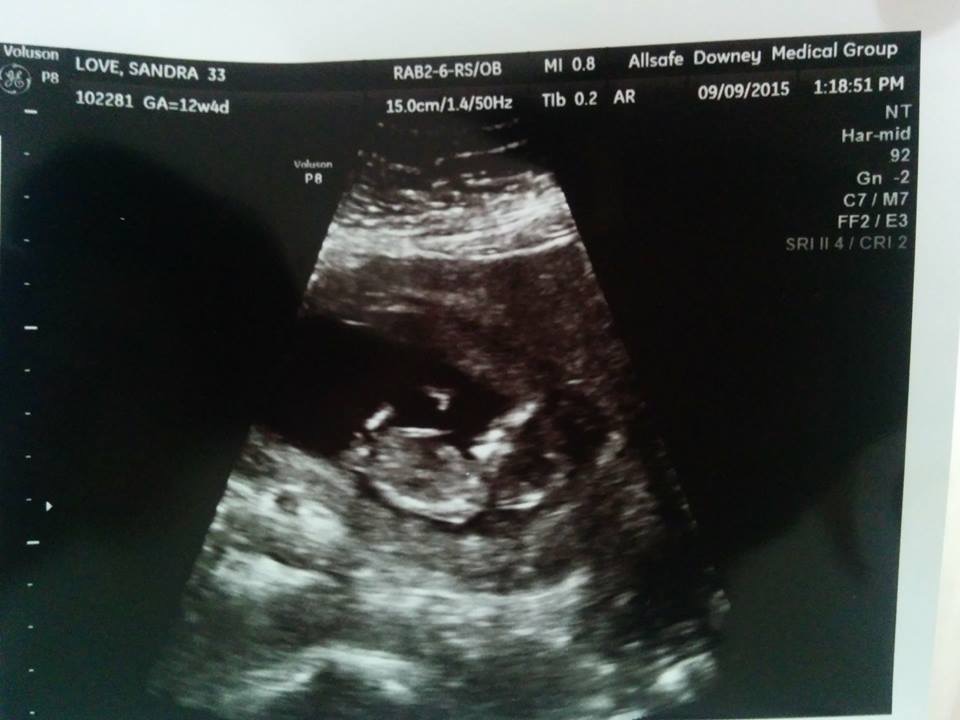

Would love to hear people' guesses. I'm having a hard time distinguishing between parts and shadows so if someone could point it out too that would be great. Thanks. :)

Attachment 28636